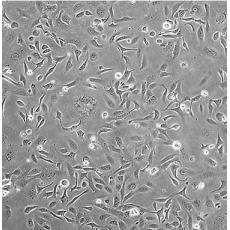

產品名稱 SK-OV-3 [SKOV3]

中文名稱 人卵巢癌細胞

組織來源 卵巢漿液性囊腺癌;腹水轉移;女性

細胞種屬 Homo sapiens, human

生長特性 adherent

培養基 McCoy's 5A+10% FBS+1% P/S

形態特征 epithelial

傳代方法 1:2-1:4

細胞描述 SK-OV-3 cells are resistant to tumor necrosis factor and to several cytotoxic drugs including diphtheria toxin, cis-platinum and adriamycin.